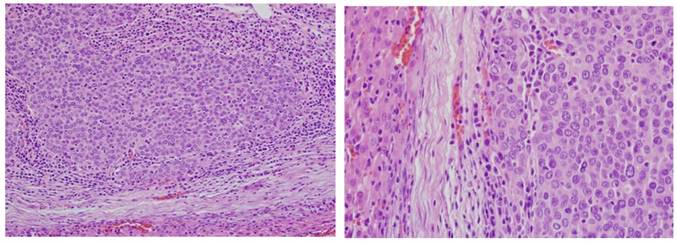

After the rabbits were sacrificed, gross pathology and histology was performed. Liver histology demonstrates a heterogeneous appearance to the tumor (Fig 4,5).

Figure 5

Histology. Hematoxylin & Eosin staining was performed confirming tumors within the liver on 10th day (H&E ×200)(A), and 10th day (H&E ×400)(B).